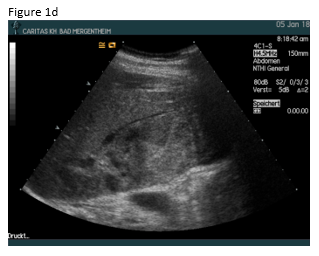

A 49 year old patient was admitted to the hospital for sepsis and shock of unknown origin. The patient presented with signs of sepsis and hemodynamic instability that justified an urgent approach including complex intensive care and intubation. Bedside ultrasound (US) found ascites and an abscess in the right liver lobe (9 cm) (Figure 1a). The patient was treated with broad-spectrum antibiotics and puncture and drainage of the abscess (Figures 1 a-c and 2 a-b). In addition, a biopsy was taken from the periphery of the lesion. A few days after the removal of the drainage the patient presented with a progressive elevation of liver enzymes. US revealed a cystic lesion measuring 30 mm that was proximal to the drained abscess (Figure 1a). Color Doppler Imaging (CDI) showed arterial flow inside the lesion, and contrast enhanced ultrasound (CEUS) showed early arterial enhancement and turbulent flow with a “to-and-fro” sign, suggestive of a pseudoaneurysm (Figure 1b). There was also a heterogeneously vascularized lesion with enhancing septae in the surrounding liver parenchyma (Figure 1c) . A few days later the patient presented with tachycardia and a drop of hemoglobin from 10 g/dl to 7 g/dl. US revealed spontaneous thrombosis of the pseudoaneurysm (Figure 1d) with intra - and perihepatic hemorrhage (Figure 1e).

Figure 2: Computed tomography (CT)showed abscess formation before drainage and perihepatic ascites (a). Twelve days after drainage removal a CT follow-up showed hyperenhancing intrahepatic lesion in proximity of the abscess, suggestive of a pseudoaneurysm (b). CT confirmed the spontaneous thrombosis of the pseudoaneurysm (c).